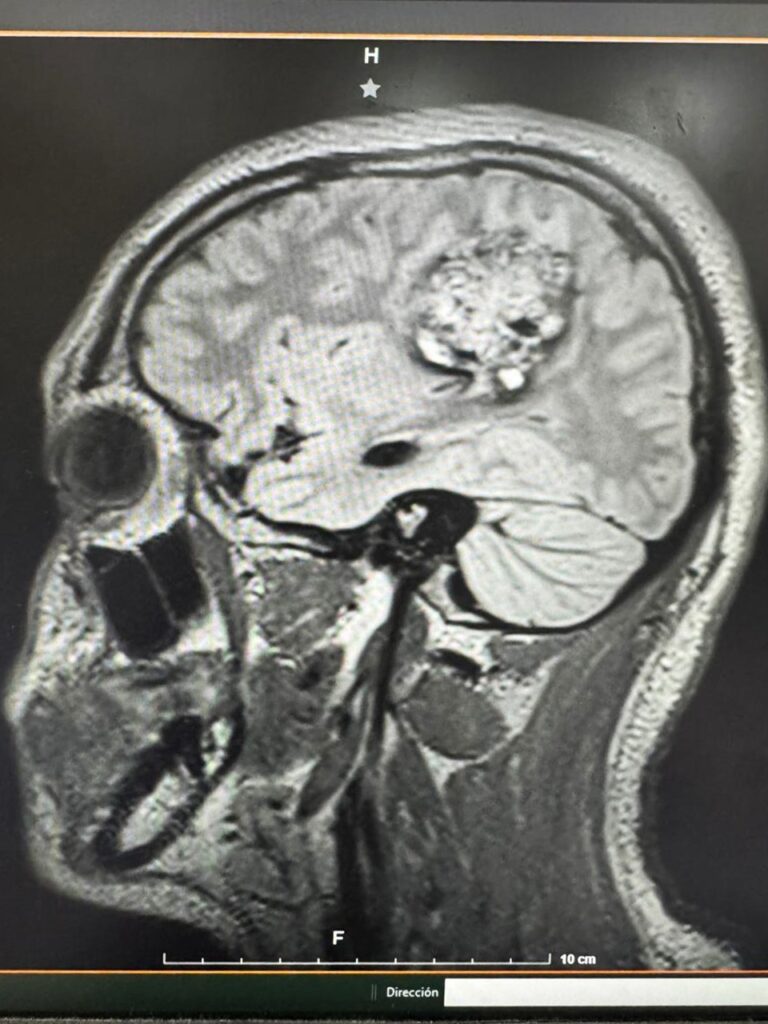

En la Unidad Médica de Alta Especialidad del IMSS en Yucatán, un grupo de especialistas realizó por primera vez una craneotomía con un paciente consciente. Francisco, originario de Cancún, había llegado con crisis convulsivas, pérdida del habla y dificultad para moverse. Los estudios revelaron un cavernoma, una lesión vascular compleja ubicada en una zona del cerebro relacionada con el lenguaje y el movimiento.

El neurocirujano pediatra Gabriel Cachón Cámara encabezó la intervención junto con un equipo de anestesiólogos y neurofisiólogos. Utilizaron la técnica “despierto-dormido-despierto”, que permite mantener al paciente consciente durante etapas clave de la cirugía. Así, pudieron evaluar en tiempo real sus funciones del habla y sus movimientos mientras le extirpaban un tumor de cinco centímetros.

La tecnología de navegación cerebral, similar a un sistema GPS, guió cada milímetro de la operación. El objetivo era retirar la lesión y preservar las capacidades motoras y cognitivas del joven atleta.

La cirugía duró seis horas. En ese tiempo, el equipo médico mantuvo la precisión y la calma que exige un procedimiento pionero. Al finalizar, el tumor había sido retirado por completo. Francisco fue trasladado a terapia intensiva, donde permaneció una semana bajo observación. La recuperación avanzó con éxito: la herida cicatrizó, no quedó lesión residual y su movilidad regresó.